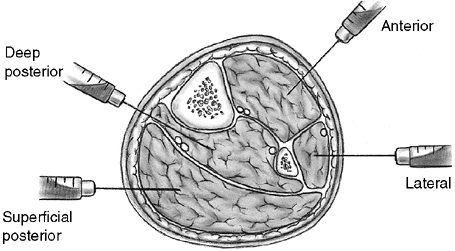

doubt (76) (Fig. 33.6). The pressure threshold for fasciotomy is

within 30 mm Hg of the patient’s diastolic pressure (76).

![]() |

Figure 33.6

Orientation and entry points for measurement of compartment pressures. (From Gulli B, Templeman D. Compartment syndrome of the lower extremity. Orthop Clin North Am 1994;25: 677, with permission.) |